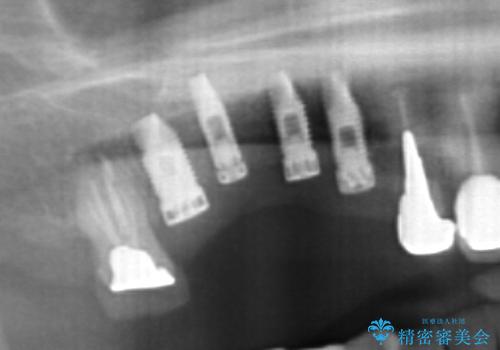

- 他院で1本インプラントを入れたまま治療に通うことができなくなり、途中からの治療を希望され来院されました。

既に埋入されているインプラントは位置が悪いのでそのまま骨内に留置することとし、新たに咬合機能を回復すべく3本のインプラントを埋入すると同時に吸収した骨幅を増やし、安定してインプラントで噛める環境整備を目指します。

- 120万円(インプラント×3 チタンカスタムアバットメント×3 メタルボンドクラウン×3 骨造成 歯肉移植)費用は治療当時の料金となります